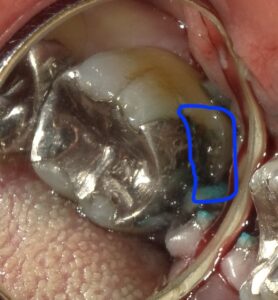

歯肉を切開し開いて青で囲った部分の虫歯を露出させます。

セメントで塞いだところです。